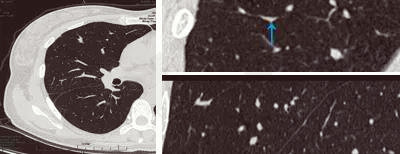

無獨(dú)有偶,34歲的張女士在一次體檢中發(fā)現(xiàn)肺部有肺磨玻璃影,在結(jié)節(jié)的性質(zhì)沒有確定前,她焦慮萬分,“我沒有咳嗽又沒有發(fā)燒怎么會(huì)有肺結(jié)節(jié)呢?”“肺磨玻璃結(jié)節(jié)是不是就是肺癌?”“要手術(shù)嗎?” ……帶著一連串疑問,她來到肺結(jié)節(jié)影像專科門診就診,經(jīng)影像??漆t(yī)生的檢查識(shí)別,明確診斷為斜裂局部胸膜增厚所致假病灶,從而徹底解除了張女士的擔(dān)憂。

局部胸膜增厚